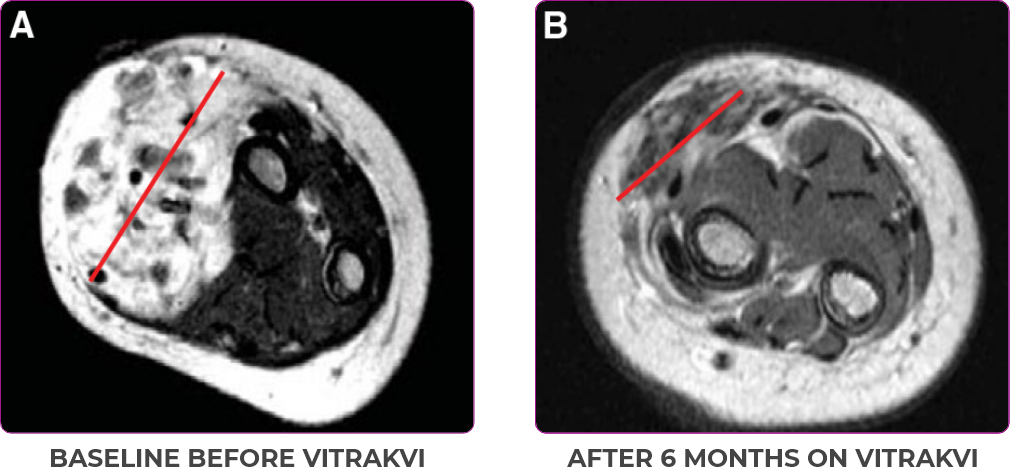

PATIENT CASE:

INFANTILE FIBROSARCOMA

OF SOFT TISSUE1

- 5-month-old with IFSa

- Progression after chemotherapy

- Confirmed PRa after 4 cycles of VITRAKVI® (larotrectinib)

- Referred for definitive limb-sparing surgery after 6 cycles

of VITRAKVI; achieved pCRa,b

Response to VITRAKVI1

- Patient achieved a confirmed partial response after 4 cycles of VITRAKVI with a 45% reduction in tumor burden

- Following 6 cycles of VITRAKVI, the patient was referred for definitive limb-sparing surgery

- Pathology revealed a complete pathologic response and clear resection margins with scar tissue noted

Reduction in tumor burden1

MRIa imagery of the brain. Red line indicates the maximum dimension.1

aMRI, magnetic resonance imaging.

Pre- and post-treatment imaging, by DuBois SG et al, is licensed under CC BY 4.0.